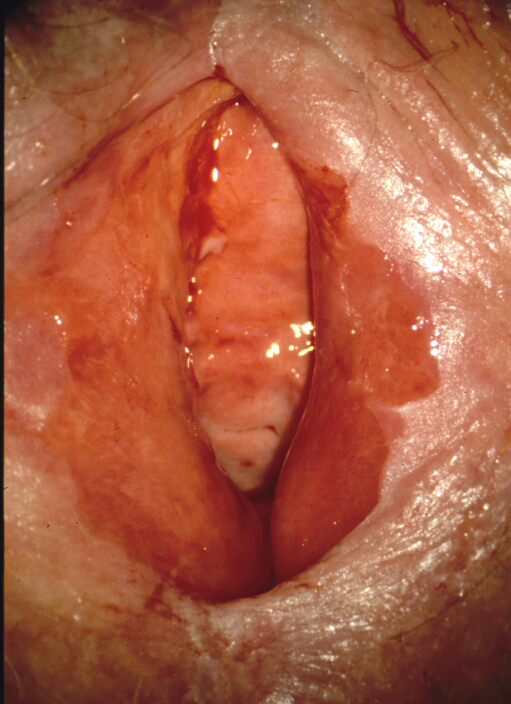

The clinical picture of a fungal infection can differ considerably. Usually redness is more or less intense, occasionally also a slight swelling, usually a fluffy, yellowish vaginal discharge is present (Figure 1). Microscopically almost always fungal elements and granulocytes can be seen if appropriate samples are taken. Pseudomycelium is almost always proof of an infection by Candida albicans, the most common and most important causative agent of genital fungal infection. A culture is necessary when symptoms are present, but no fungi are seen, or if only small germinating cells (e.g. C. glabrata) or large elongated germinating cells (indicating Saccharomyces cerevisiae = baker's yeast) are found in recurrent or chronic courses.

Not every fungal involvement, nor each colonization of Candida albicans causes inflammation and thus discomfort. A therapy is only indicated in case of complaints or during pregnancy.

Many substances and galenic forms are available for the treatment of candidiasis. Occasional candidiasis should be treated locally, chronic recurrent candidiasis with severe infestation of the vulva should be treated orally with, for example, fluconazole (150 mg once or in severe cases 2 to 3 times every other day). Symptoms should disappear after therapy, for example on the 4th to 6th day. If this is not the case, the fungus is not the cause of the discomfort or just an additional disease. Therapy of the partner is recommended for chronic recurrent candidiasis. Regular skin care leads in the long term to an epithelial improvement and thus to reduction of pathogens from the skin. A biopsy should be performed if the skin alterations persist despite optimal therapy.